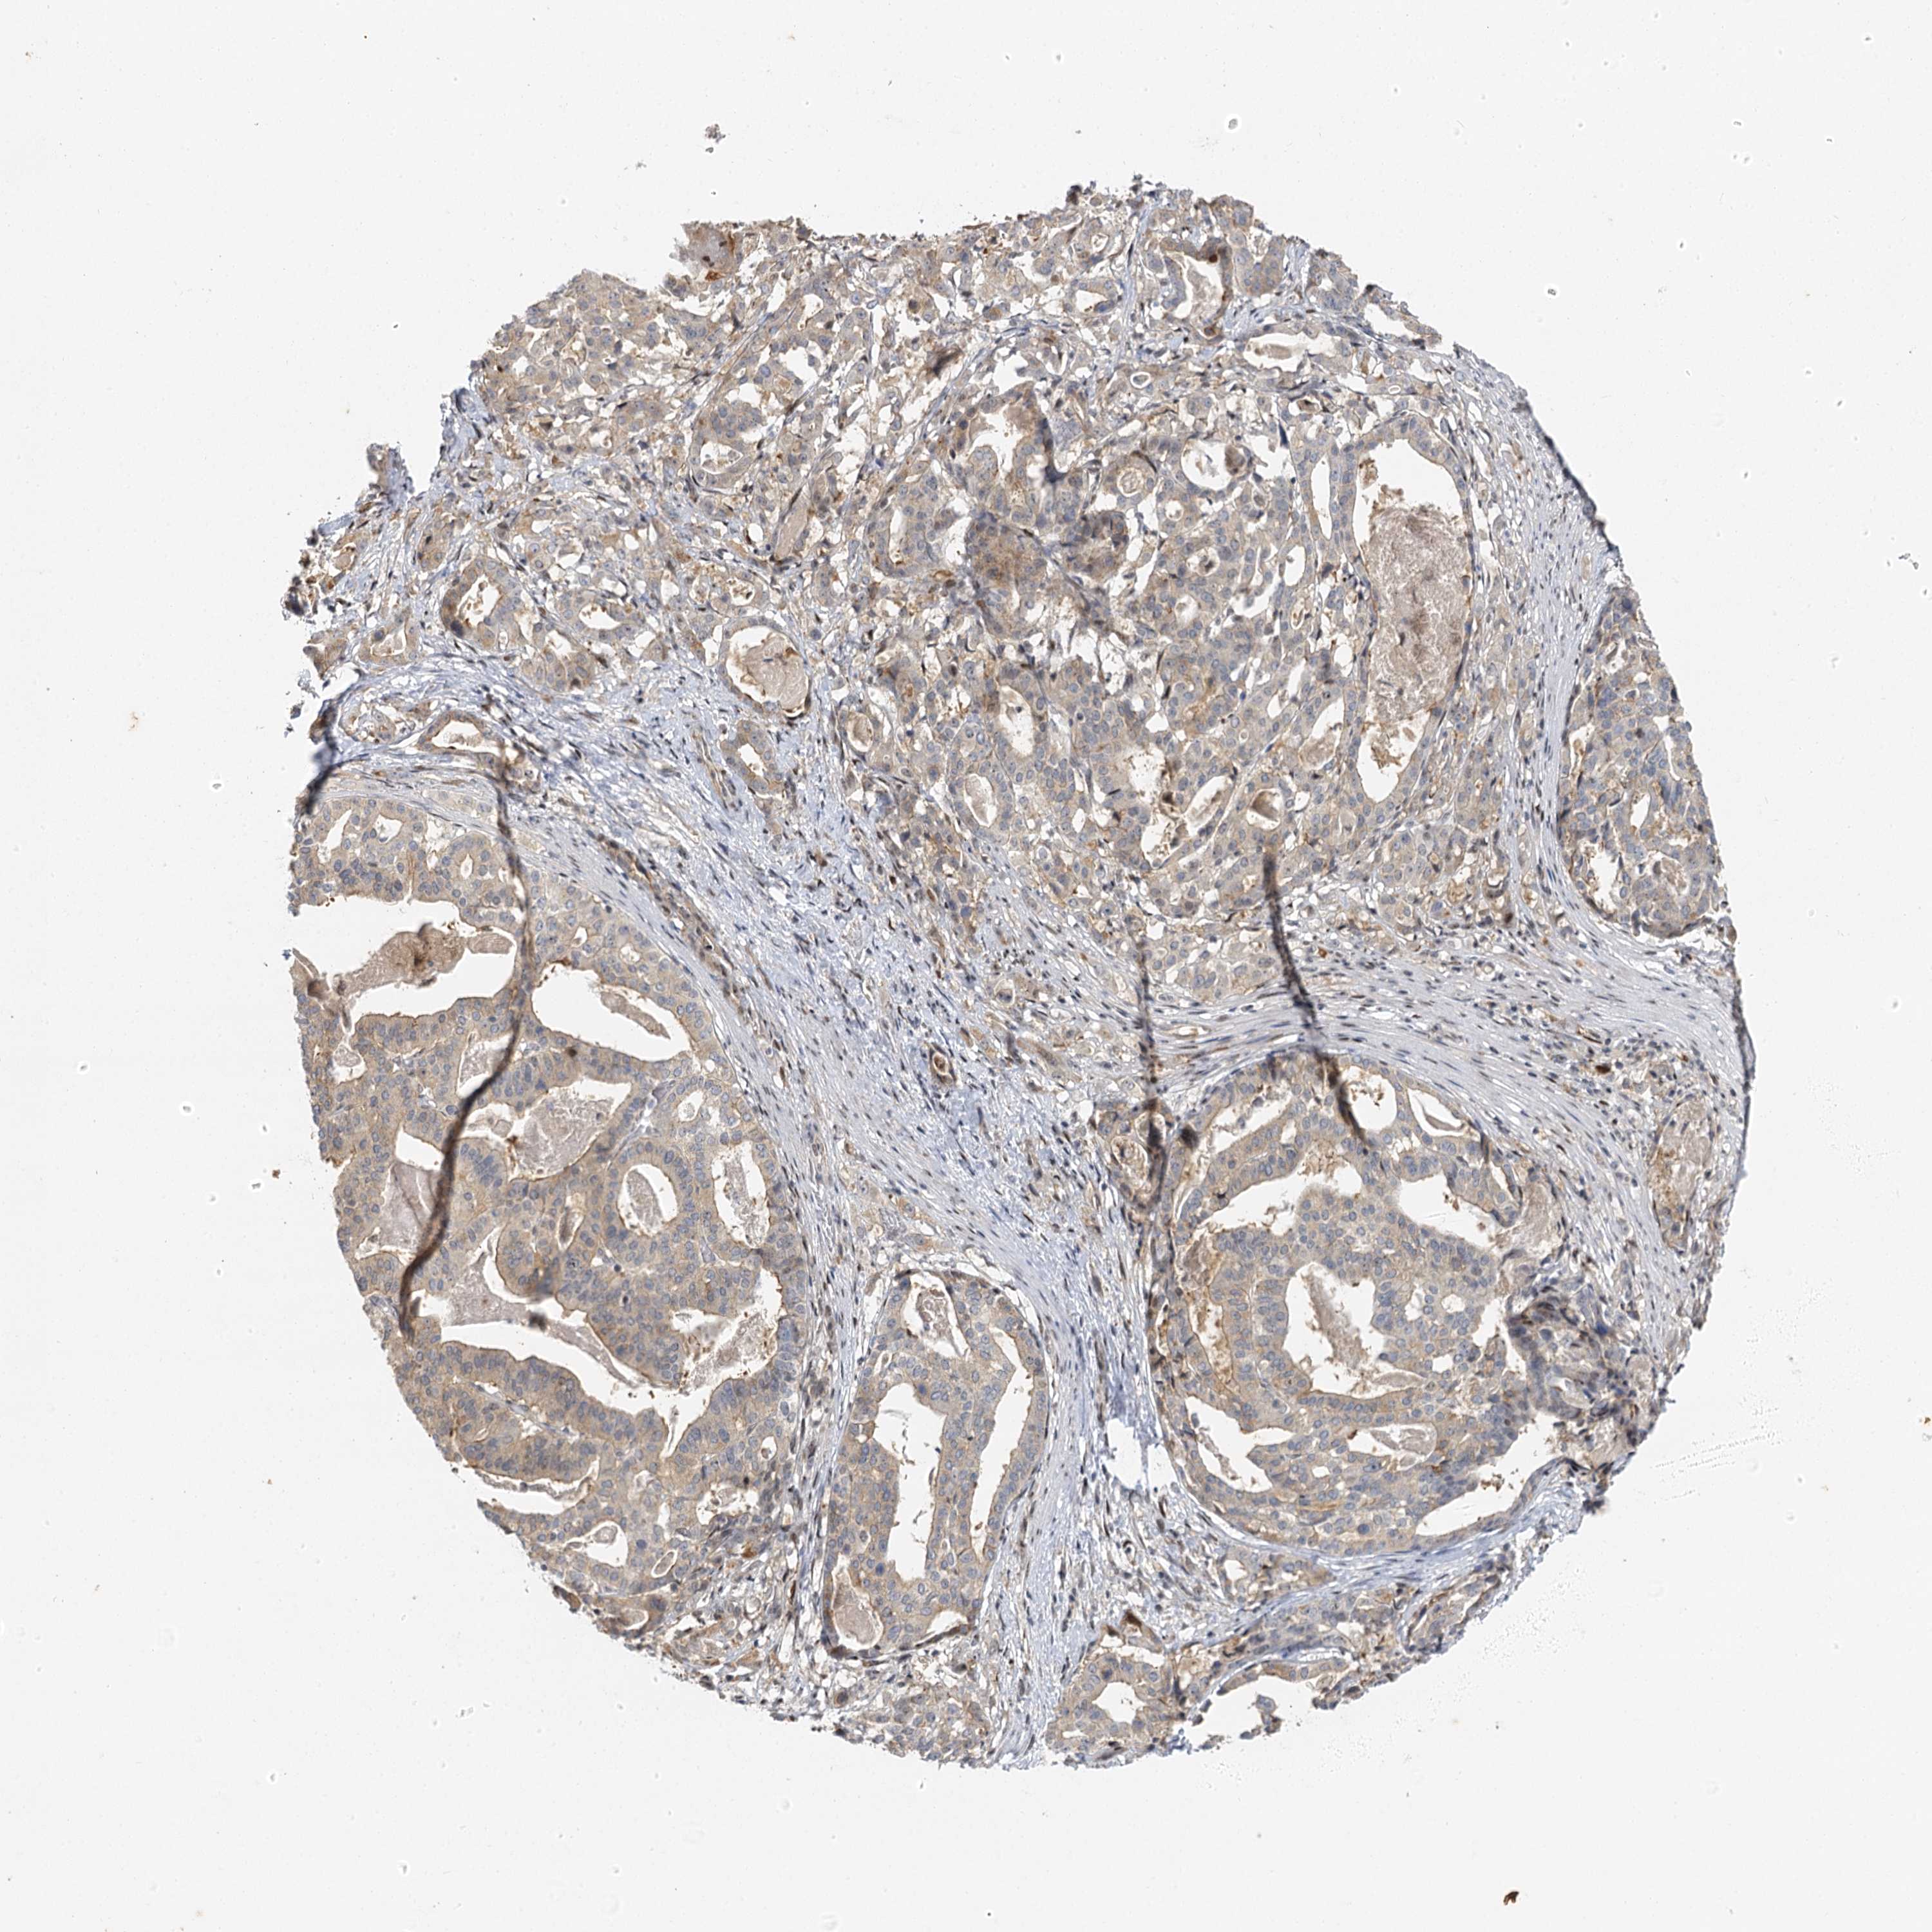

STOMACH CANCER - Protein expressioni

A mouse-over function shows sample information and annotation data. Click on an image to view it in a full screen mode. Samples can be filtered based on level of antibody staining by selecting one or several of the following categories: high, medium, low and not detected. The assay and annotation is described here.

Note that samples used for immunohistochemistry by the Human Protein Atlas do not correspond to samples in the TCGA dataset.

Antibody stainingi

Antibody staining in the annotated cell types in the current human tissue is reported as not detected, low, medium, or high, based on conventional immunohistochemistry profiling in selected tissues. This score is based on the combination of the staining intensity and fraction of stained cells.

Each image is clickable and will lead to virtual microscopy that enables deeper exploration of all samples and also displays staining intensity scores, fraction scores and subcellular localization as well as patient and tissue information for each sample.

Antibody HPA013162

Antibody HPA036652

Antibody CAB032830

Staining

High

Medium

Low

Not detected

Intensity

Strong

Moderate

Weak

Negative

Quantity

>75%

75%-25%

<25%

None

Location

Nuclear

Cytoplasmic/membranous

Cytoplasmic/membranous,nuclear

Adenocarcinoma, NOS

Adenocarcinoma, High grade